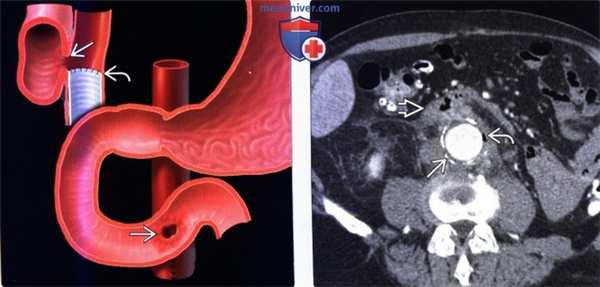

(Слева) На рисунке показана фистула между поперечной частью двенадцатиперстной кишки и аортой в области шва, наложенного на стент и аорту.

(Справа) На аксиальной КТ с контрастным усилением у мужчины 70 лет, у которого через месяц после реконструктивной операции по поводу аневризмы брюшной аорты повысилась температура тела и возник гематемезис, визуализируется кальцинированная стенка аорты, обернутая вокруг синтетического стента. Между стенкой аорты и стентом определяется скопление газа что означает присоединение инфекции либо наличие фистулы. Обратите внимание на наличие компонента мягкотканной плотности вокруг аорты и третьей части двенадцатиперстной кишки.